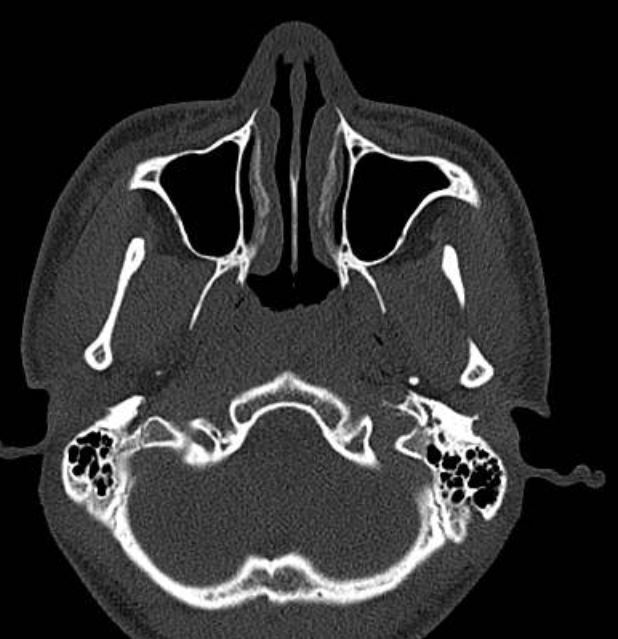

做了鼻内镜和鼻窦CT检查后发现主要的问题是下鼻甲肥大,堵塞了鼻腔。这种情况如果药物治疗效果不好,通过鼻内镜微创手术是可以解决的。